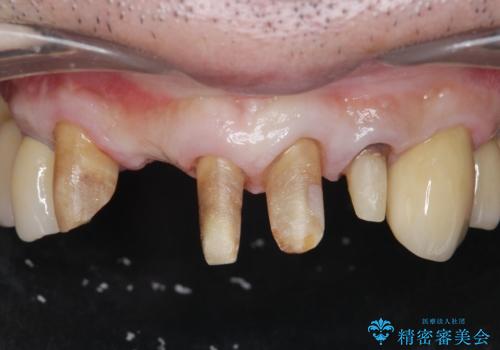

- 前歯の見た目をなんとかしたい、とセラミック治療を希望され来院されました。

セラミック治療を行う前に歯周病の問題を解決すべく歯周外科を行い歯周ポケットを除去し整備したのちセラミックブリッジ・クラウンの製作を行います。

歯周外科を行ったことで非常に安定した歯周環境となり、引き締まった歯ぐきとなりました。